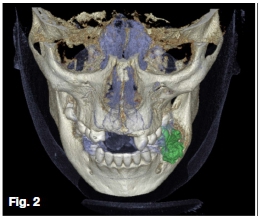

CBCT imaging and analysis was performed. Observe unilateral expansion by the distending soft tissue outline illustrated through 3D rendering (Figure 2). Sagittal oblique (Figure 3) and axial (Figure 4) slices depict a round heter-ogenous predominantly high-density lesion with an encompassing thin uniform less dense peripheral band. Irregular root resorption, displacement of the inferior alveolar nerve canal, buccal-lingual cortical expansion, thinning, and interruption was apparent. Irregular thickening at the inferior border and surrounding osteosclerosis were noted. A macroscopic view (Figure 5), photomicrograph (Figure 6), and conventional radiograph (Figure 7) of vertically sectioned surgical specimens of similar lesions. Note the intimate relationship with the tooth roots.